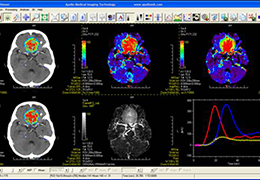

View X-Ray CT & MRI Scans Fast and Easily

Designed for surgeons, Pro Surgical 3D makes it easy to view patient scans quickly. Pro Surgical 3D facilitates the optimal 3D treatment and assessment workflows based on X-ray CT and MRI scans – and best of all, it’s FREE!

Traditional multi-planar slicing

High-quality and fast 3D reconstruction and 3D rendering

Multi-planar slicing.